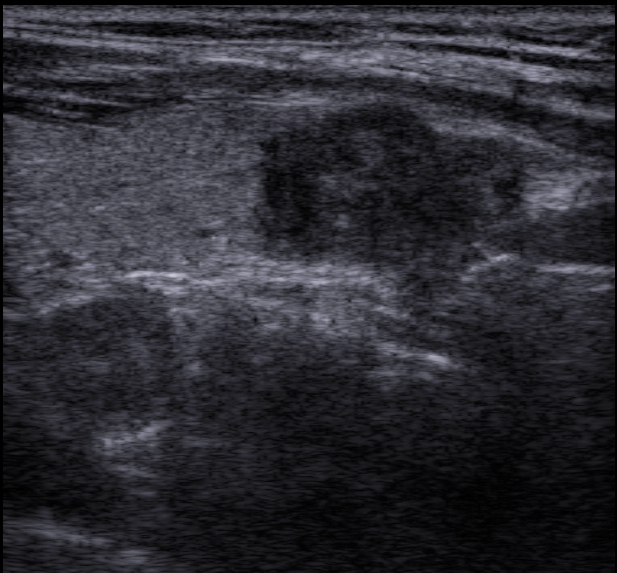

BIRADS 4 - подозрительно в отношении злокачественности. Неровные/нечеткие края, микрокальцинаты, неоднородные образования, вертикально-ориентированные образования с тенями и без попадают сюда. Как правило выполняется биопсия или пункция (вторая чаще). Выделяют еще три подкатегории, но я не стану вас этим грузить, так как даже большая часть врычей УЗИ, особенно в поликлиниках, не выставляют подкатегории.

На грани четверки и пятерки